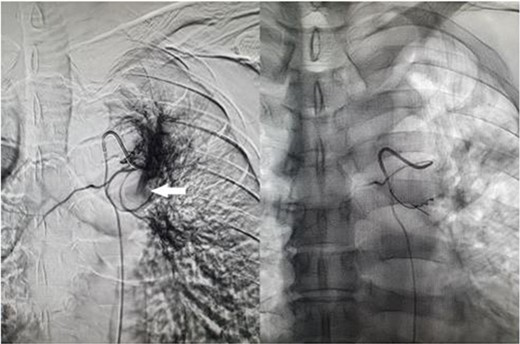

Fluoroscopic image of bronchial artery catheterization and angiogram (left); flow of contrast into the pulmonary artery branch (white arrow) which quickly dissipates, and postembolisation image (right) with microcoils in the treated artery.

A 57-year-old male presented to the Emergency Department unwell with central chest pain, dyspnoea, and haemoptysis. CT pulmonary angiogram demonstrated bilateral cavitating pneumonia. Irregular nonenhancement of a segmental pulmonary artery in the left upper lobe was also noted (Fig. 1). CT thorax in systemic arterial phase demonstrated enhancement of this segmental branch in the left upper lobe (Fig. 1). These findings are due to reversal of flow in the pulmonary artery branch due to higher pressure blood from the bronchial artery passing through the fistula. The patient was brought to interventional radiology for further investigation and management. An initial nonselective descending aorta angiogram demonstrated the bronchial artery-pulmonary artery fistula in the left upper lobe. Selective cannulation of the enlarged left bronchial artery was then performed followed by microcatheter cannulation of the main feeding vessels to the fistula. The vessels were embolized to stasis with 400-μm microparticles (Embozene 400) and microcoils (Fig. 2). The patient tolerated the procedure well and had an uncomplicated postprocedural course. Pansensitive tuberculosis detected on sputum sample. Treatment with Rifater, pyridoxine, and ethambutol were commenced. No further episodes of haemoptysis have been noted to date on clinical follow-up.